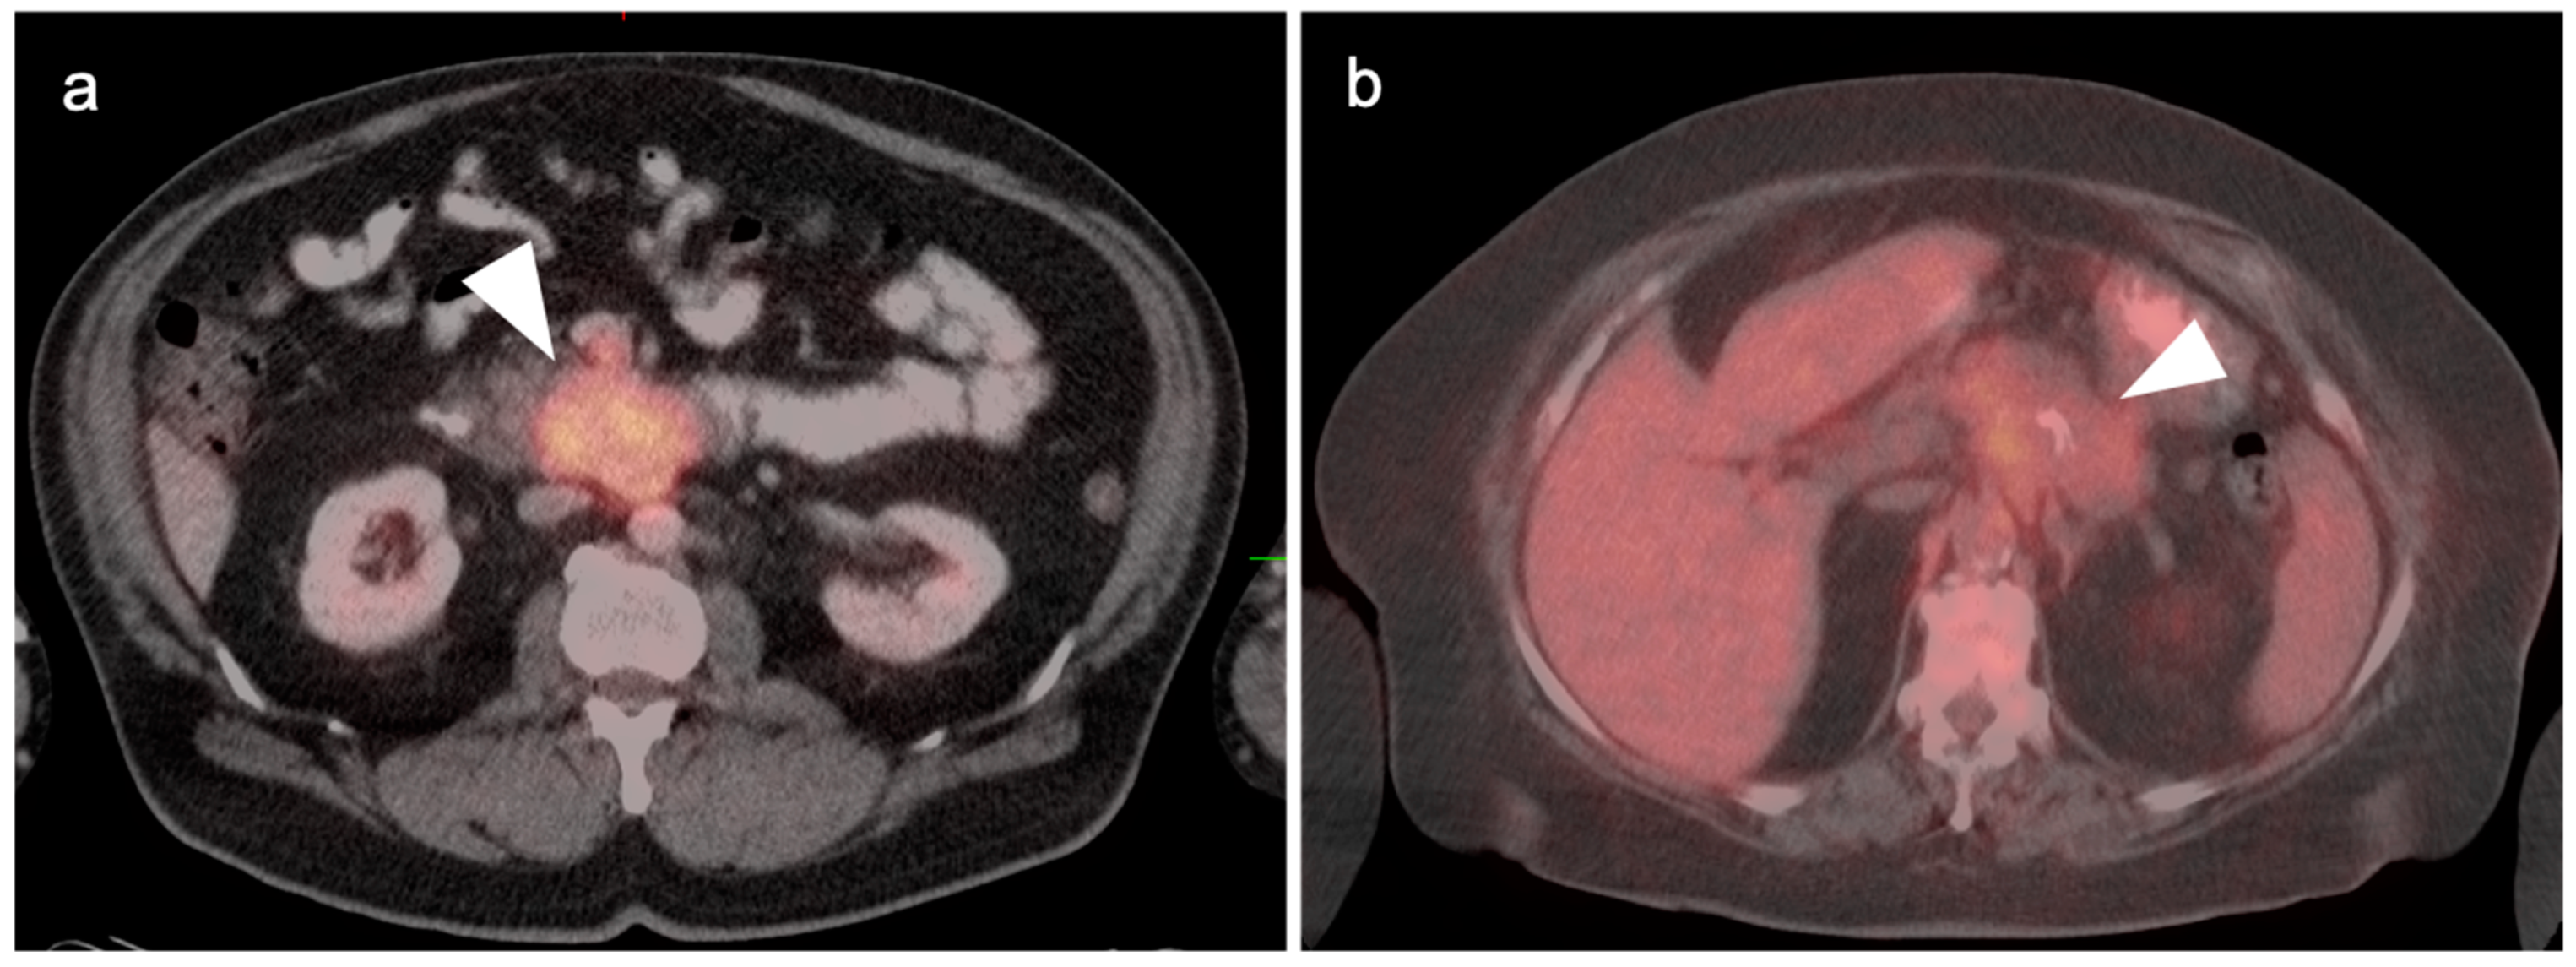

5. Cholangiocarcinoma